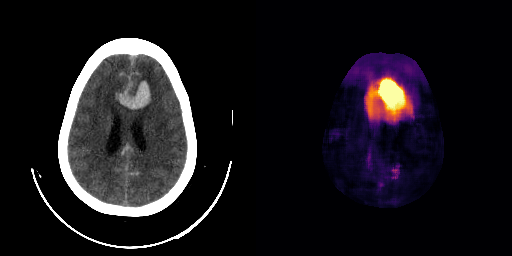

healthy

We show some slices with examples of ICH in \figurereffig:qualitative_ich as well as surface renderings of scans of subjects with cranial fractures in \figurereffig:qualitative_fractures. (As a reference we also included the same examples for the AE in Appendix D in \figurereffig:qualitative_ich_ae.) It is noticeable that the reconstruction error is high where there is an anomaly. The reconstruction error generally seems to continuously depend on the amount of the patch that is anomalous, as the error maps generally seem to be rather smooth.

The performance for the models used for \figurereffig:qualitative_ich and LABEL:fig:qualitative_fractures are shown in \figurereffig:roc_performance. We observe see that the detection of fractures is the more challenging task for our method than the detection of ICH. This might be due to the smaller number of scans available to evaluate it on (see Appendix B). To put these results in context we provided a table with the inter rater agreement on these tasks in Appendix B: The performance in terms of AUROC is around lower than the average raters.